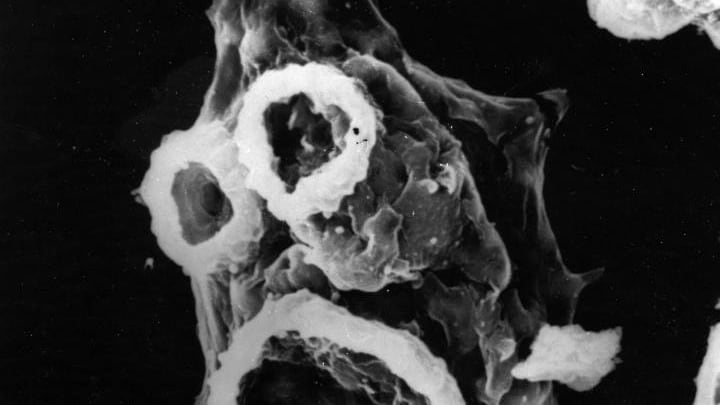

La Naegleria se encuentra en cuerpos de agua cálidos, como lagos, ríos y hasta aguas termales. También puede encontrarse en el suelo. Sin embargo, solo un tipo de esta bacteria afecta a los humanos: la Naegleria fowleri.